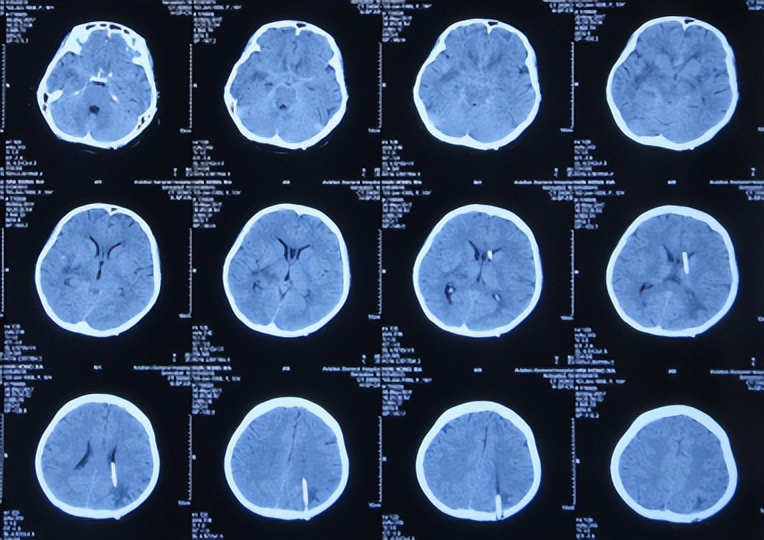

但发病后5天即2017年3月25日,从学校宿舍的上铺下来时因发热虚弱摔下,右眼眶外伤,就诊于第1家的陕西省西安某三甲医院,查脑CT( 图-1 )后认为右额颞部硬膜下有血肿,胸部X线检查未见异常(片子丢失)。

图-1: 2017年3月25日脑CT